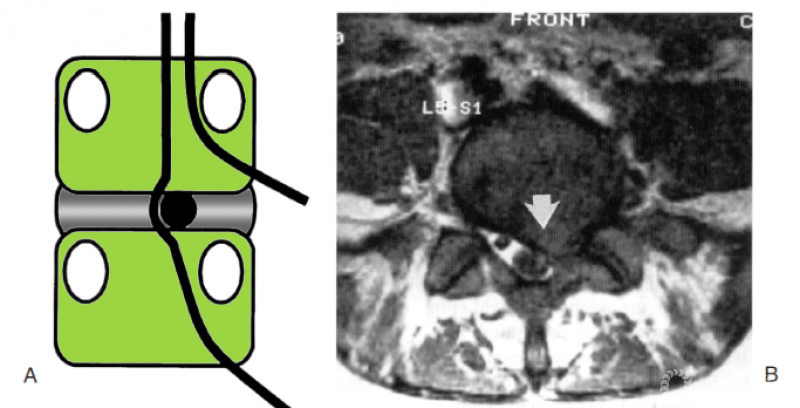

图18.8 对各层病变判读的图解。A:图示为第1层的椎间盘突出;B:T1加权轴位MRI显示第一层的椎间盘突出(箭头)

图18.9 A:椎间盘突出最常见的移位方式为突破自身解剖节段的第1层,进入相邻下位节段的第3层;B:T1加权矢状位MRI显示L5-S1大块的椎间盘突出向下进入S1节段的第3层(箭头)